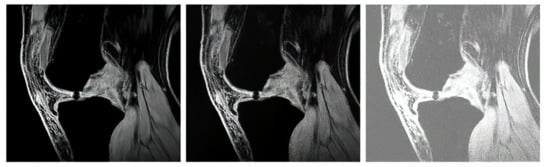

The proton density-weighted MR imaging is able to recognize in contrast the cartilage defects and abnormal cartilage composition in their tissues. This imaging sequence enables a suitable investigation of the cartilage morphology, ligaments, and menisci. The fat-saturated proton density-weighted images are suitable for the investigation of a low-signal intensities, which is a typical case of early cartilage loss. Therefore, this technique is well suited for the examination of osteoarthritis. As an example of the articular cartilage data, we provide a comparison of various sequences from the same cartilage area (Figure 4).

Proton density sequence plays an indispensable role in structural investigation of the early stage of articular cartilage loss. Here, only a weak contrast between a common cartilage surface and such pathological findings are notable. Therefore, for our analysis these data are substantially important. To objectivize such findings, we provide the example (Figure 5) from our dataset, where such investigations can be observed.